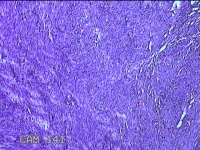

子宫肌瘤

性别

女

年龄

38岁

临床诊断

一般病史

发现子宫肌瘤复发7年余。

标本名称

大体所见

灰白粉红色结节样肿物8.5x5.5x4cm一个,表面糜烂,切面灰白色,编织状,质中。

富于细胞性平滑肌瘤

考虑富细胞平滑肌瘤。

组织处理和染色都不太理想。